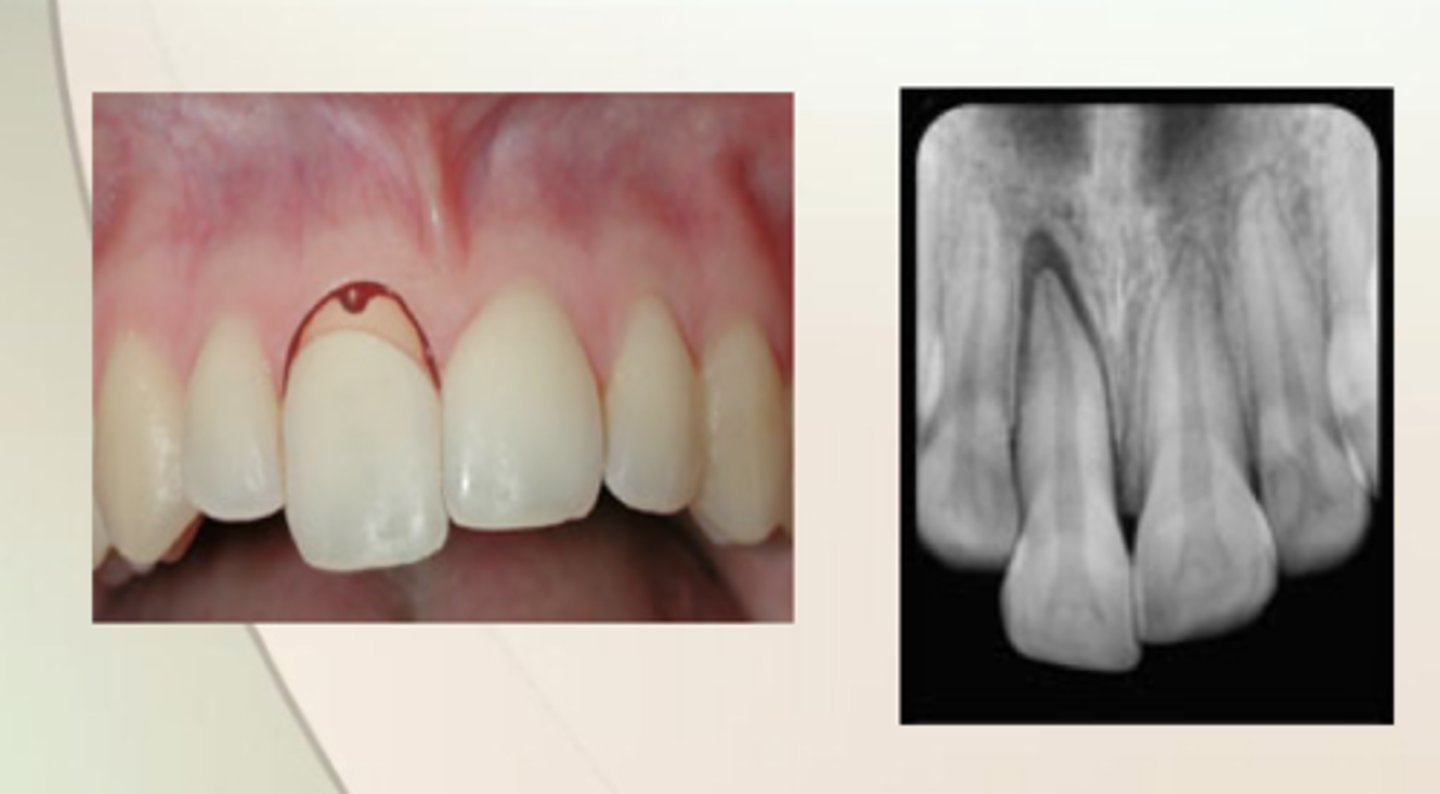

Intrusive Luxation

tooth has almost or completely disappeared into the socket and can be palpated labially

How long does it take for a tooth to reposition?

6 months